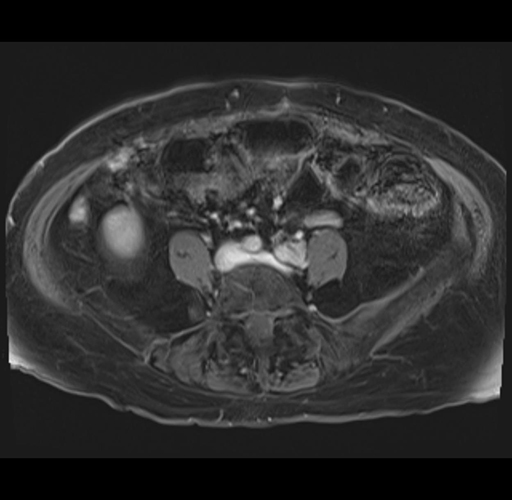

MRI T1